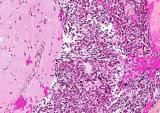

Генерация циркулирующих опухолевых клеток (ЦКО), ключевой этап метастазирования опухоли, происходит во время хирургической резекции опухоли, часто выполняемой под общим наркозом. Для него используется...

Ученые определили специальный белок, который, по-видимому, помогает предотвратить попадание опухолевых клеток в кровоток и распространение их в другие части тела...

Исследователи из Каролинского института в Швеции опубликовали в журнале Cancer Discovery результаты нового исследования, демонстрирующие, как фармакологическая активация белка p53 усиливает...